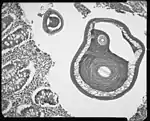

Trichuris trichiura

Trichuris trichiura, ou Trichocephalus trichiuris, est une espèce de nématodes (les nématodes sont un embranchement de vers non segmentés, recouverts d'une épaisse cuticule et menant une vie libre ou parasitaire). C'est l'un des parasites du tube digestif humain, dont des œufs fossilisés sont encore trouvés sur des lieux de fouilles archéologiques préhistoriques[1].

C’est un nématode de 3 à 5 cm de long.